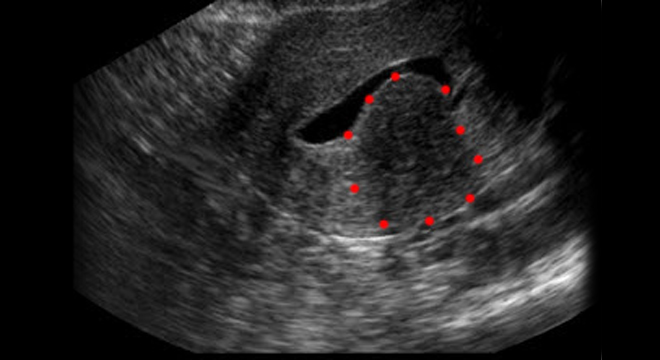

Myom der Gebärmutter: Ultraschalluntersuchung

Zur Diagnose eines Myoms werden verschiedenen Untersuchungen und Abklärungen durchgeführt. Dazu gehören unter anderem:

• Ultraschall